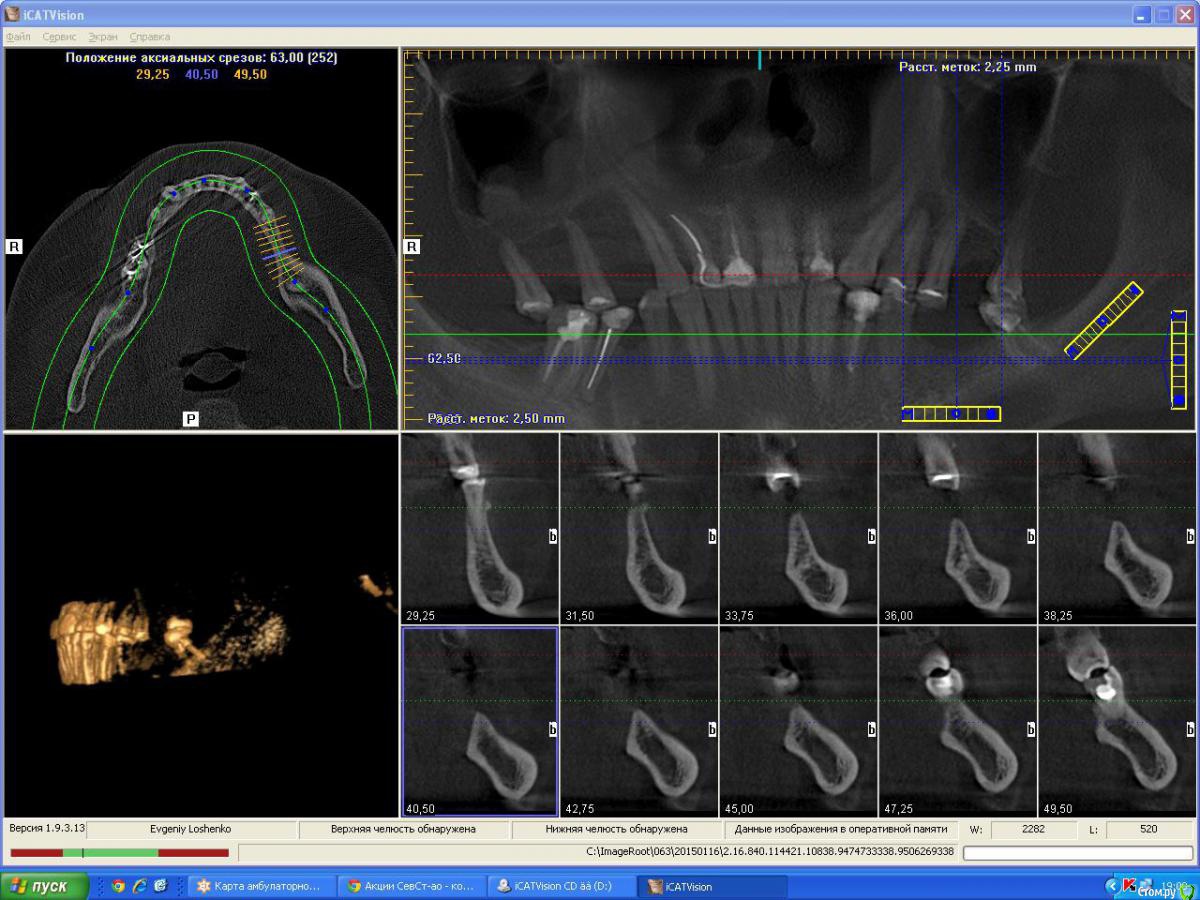

denis1987 Опубликовано 25 февраля, 2015 Поделиться Опубликовано 25 февраля, 2015 Вот такой вот пациент , с адентией в 1 , 2 , 3 и 4 сегментам. Фото прилагаются. Ссылка на комментарий

denis1987 Опубликовано 25 февраля, 2015 Автор Поделиться Опубликовано 25 февраля, 2015 Вот ничего другого на ум не приходит как аугментация костными блоками аутогенными, по крайней мере в 1 и 3 сегментах. Во 2м егменте расщепление + закрытый синус, в 4м вроде как хороший аэродром. Интересует мнение форумчан. Ссылка на комментарий

Aquarius Опубликовано 25 февраля, 2015 Поделиться Опубликовано 25 февраля, 2015 (изменено) Ну в области 14-го ламина точно сработает. И Вы планируете аугментацию на неправильно выставленных срезах!!! Изменено 25 февраля, 2015 пользователем Aquarius Ссылка на комментарий

denis1987 Опубликовано 25 февраля, 2015 Автор Поделиться Опубликовано 25 февраля, 2015 Денис,когда планируете аугментацию? Если не в ближайшие несколько дней, то я постараюсь выложить отпротоколированный кейс с ламиной в области 14. Может что-то возьмете на вооружение. Вроде наконец учёл все ошибки)) И что-то выросло.Все , я понял про что вы говорили в плане среза , на самом деле кусок альвеоляра не влез , настроил норм , но все равно картина не сильно изменилась к сожалению ( Ссылка на комментарий